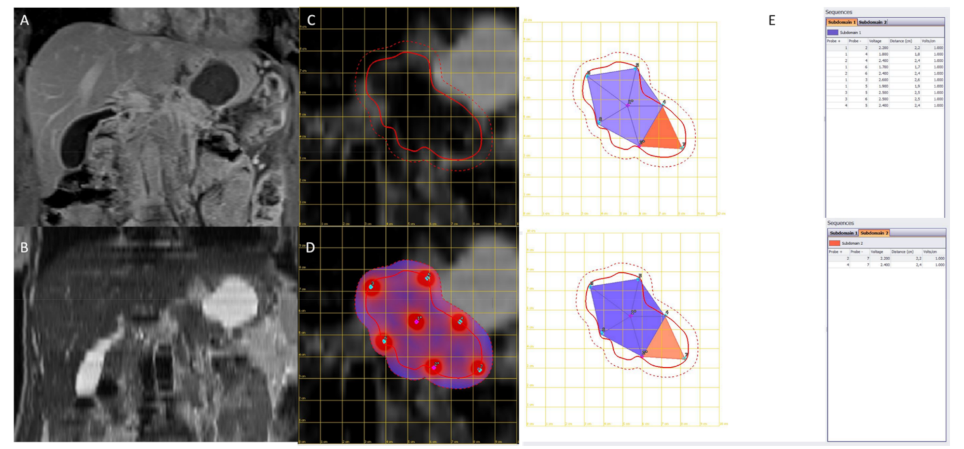

2.2.Treatment Protocol

2.3.Imaging Techniques

3.2. Secondary Endpoints Assessment (Feasibility and Safety)